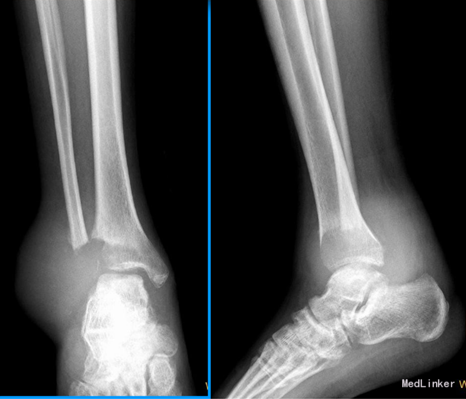

患者男性,36岁,因扭伤后右踝肿痛1月余入院。患者1月余前因扭伤致右踝肿胀、疼痛,外院就诊,诊断为“右胫骨撕脱性骨折”,予石膏固定、草药外敷等治疗后未见好转,遂至我院治疗。

查体:右外踝肿胀,皮肤颜色暗红色,皮温增高,右侧踝可触及质韧肿物,基地广泛,移动度差,肿物按压有轻度胀痛,无叩痛。 辅查:右胫腓骨X线片示:右胫腓骨远端骨质缺失,周围软组织肿胀,不除外骨肿瘤,建议进一步检查。行MRI示:右胫腓骨远端肿物,考虑恶性肿瘤。实验室检查未见明显异常。